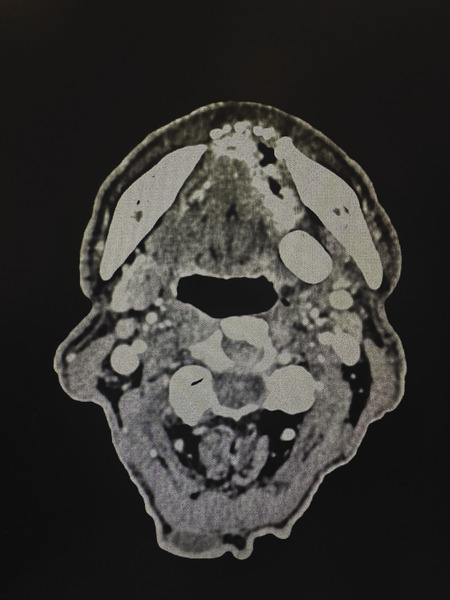

Pacjent został przyjęty 2 miesiące wcześniej na Oddział Otolaryngologii Szpitala w Lubinie, gdzie wykonano biopsję wycinkową zmiany nowotworowej dna jamy ustnej oraz badania obrazowe: tomografię komputerową (TK) twarzoczaszki i szyi z kontrastem, ultrasonografię (USG) jamy brzusznej oraz radiografię klatki piersiowej.

Ryciny 1-3 przedstawiają skany tomografii komputerowej twarzoczaszki i szyi z kontrastem, które szczegółowo dokumentują lokalizację oraz zaawansowanie zmiany nowotworowej. Ponadto materiał uzupełniają fotografie wykonane podczas zabiegu chirurgicznego, obrazujące zakres przeprowadzonej resekcji (ryc. 4 A-D).